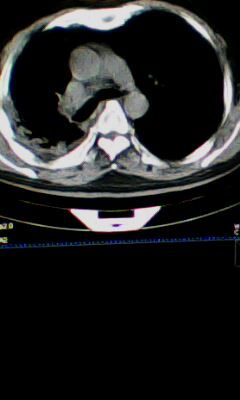

标题: CT25675:男 71 肺癌部分切除术后 3年 [打印本页]

标题: CT25675:男 71 肺癌部分切除术后 3年

两肺感染性病变,右侧肺膨胀不全,左侧上叶结节影及左侧颈部淋巴结肿大建议复查。

1)两肺感染性病变。2)右侧胸膜增厚。3)冠状动脉及主动脉钙化。